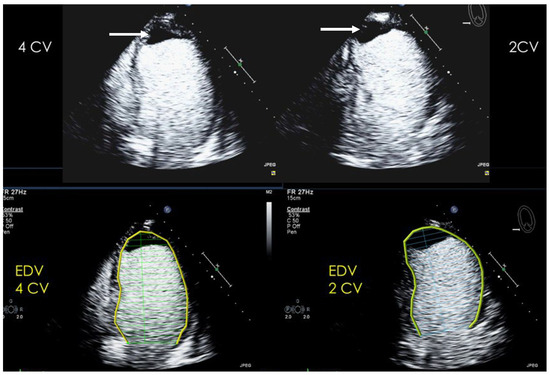

| Number |

|---|

| Localization: attached to which segments |

| Size: diameter in two planes, document in which planes measurements were performed |

| Shape: laminar, protruding, pedunculated |

| Mobility: yes/no |

| Comparison with previous echocardiogram if available |

| Imaging method | Low-MI-contrast-specific imaging and intermediate-MI-contrast-specific imaging |

| Imaging planes | standard apical views additional zoomed views sweeps through the region of the suspected thrombus |

| Sector depth/width | Entire LV + 1/3 LA to assess global/regional LV function, zoomed views of the region with the suspected thrombus |

| Focus | At the depth of the suspected thrombus |

| Gain | Adjust to avoid obscuring the thrombus by intensive opacification of the cavity |

| Contrast application | bolus injections |

| Typical findings | 1. echofree mass 2. present in two different imaging planes 3. lump or laminar shape different from trabeculations’ documented size (two orthogonal diameters in at least one of the views), location, type (laminar vs. lump, single vs. multiple), surface (smooth vs. irregular) and mobility |

| DD tumor vs. thrombus | Opacified (vascularized) masses are suggestive of tumors; the vascularization can be demonstrated with myocardial perfusion imaging. CAVEAT: There are malignant tumors which appear avascular on CEUS. Tumors often are attached to normal myocardium. |

| Alternative imaging | Thrombi: Cardiac MRI when contrast echo is not possible or non-diagnostic, cardiac CT when cardiac MRI is not available Tumors: MRI provides tissue characterization and should be performed unless there is typical myxoma (attached to the interatrial septum) |